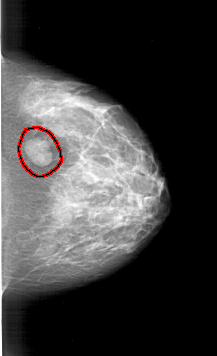

A_1394_1.RIGHT_CC

RIGHT_CC LINES 5686 PIXELS_PER_LINE 3466 BITS_PER_PIXEL 12 RESOLUTION 43.5 OVERLAY

FILE: A_1394_1.RIGHT_CC.OVERLAY

TOTAL_ABNORMALITIES 1

ABNORMALITY 1

LESION_TYPE MASS SHAPE LOBULATED MARGINS CIRCUMSCRIBED

ASSESSMENT 4

SUBTLETY 5

PATHOLOGY BENIGN

TOTAL_OUTLINES 1

BOUNDARY